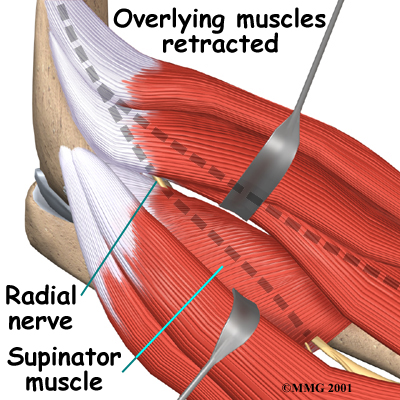

On the lateral part of the elbow, the radial nerve enters a tunnel formed by muscles and bone. This is called the .

Passing through the radial tunnel, the radial nerve runs below the . The supinator muscle lets you twist your right hand clockwise. This is the motion of using a screwdriver to tighten a screw.

After the radial nerve passes under the supinator muscle, it branches out and attaches to the muscles on the back of the forearm.

The goal of surgery for radial tunnel syndrome is to relieve any abnormal pressure on the nerve where it passes through the radial tunnel. The surgeon begins by making an incision along the outside of the elbow and down the forearm, near the spot where the radial nerve goes under the supinator muscle.

Soft tissues are gently moved aside so the surgeon can check the places where the radial nerve may be getting squeezed within the radial tunnel. The nerve can be pinched in many spots, so it is important to check all the areas that may be causing problems. Any parts of the tunnel that are pinching the nerve are cut. This expands the tunnel and relieves pressure on the nerve. At the end of the procedure, the skin is stitched together.

The following images show each step: